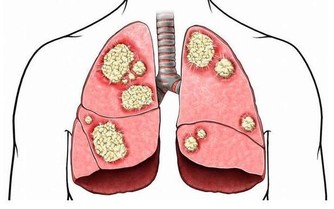

研究顯示,全球每年新發胃癌有40%以上發生在中國,而且85%以上的胃癌患者被確診時已經到了中晚期,其五年生存率迅速將到20%以下。

人們常說“人食五穀雜糧,孰能無疾”,而飲食入口,首先影響的就是胃。而且胃癌,大多是“拖”出來的!因為胃癌早期具有隱蔽性,它之所以難發現,是因為它跟普通胃病症狀很相似,而胃病又太過普遍,所以即使出現也被一拖再拖,最終到了晚期。

這3類人是胃癌“高危”人群!

患有胃癌癌前病變的人群,如:慢性萎縮性胃炎、慢性胃潰瘍、腸息肉和切除了部分胃的人群,一級家族成員中有胃癌患者的人,要特別警惕胃癌的靠近。